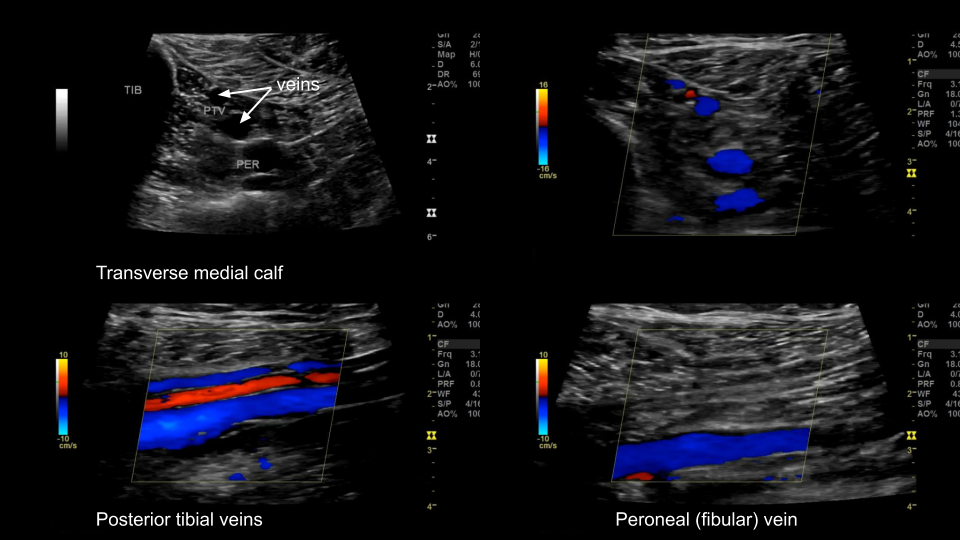

Tibio-Peroneal veins